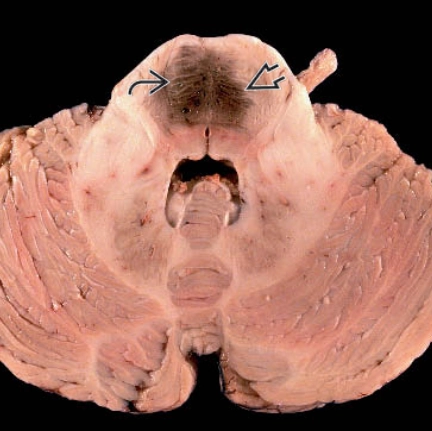

• Dị dạng thể hang ở não (Cerebral Cavernous Venous Malformations)

Dị dạng thể hang ở não (Cerebral Cavernous Venous Malformations)